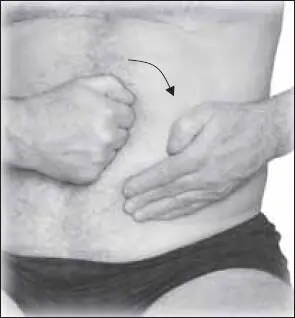

При положительной ответной реакции можно выполнить накатывание на кулак, при этом все движения надо выполнять по часовой стрелке (рис. 133).